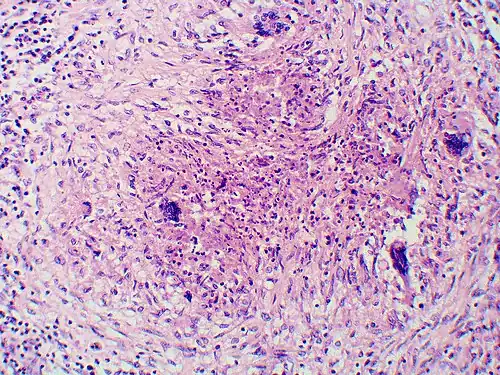

-

Granuloma with early suppuration. The fungal organisms are difficult to recognize at this low magnification. -